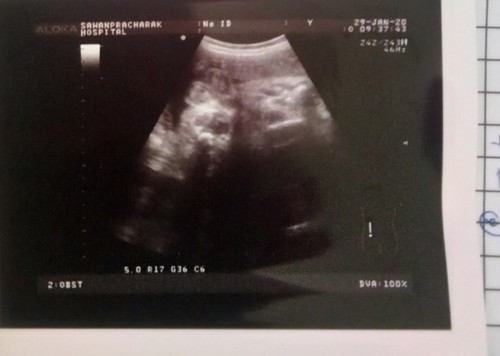

37+4 แล้วลุ้นๆๆ

ผู้หญิง หรือ ผู้ชาย